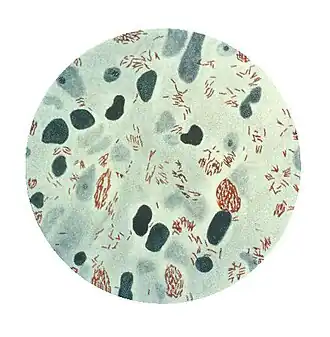

![]() Mikrofotografie Mycobacterium leprae, malé cihlové červené tyče v klastrech, odebrané z kožní léze. Zdroj: CDC | |

Mycobatecterium leprae je bakterie, která se většinou vyskytuje v teplých tropických zemích, způsobující lepru („Hansenova nemoc“). Je to intracelulární, pleomorfní, acidorezistentní bakterie. M. leprae je aerobní bacillus obklopený charakteristickým voskovým povlakem, jenž je unikátní pro mykobakterie. Ve velikosti a tvaru se velmi podobá Mycobacterium tuberculosis.